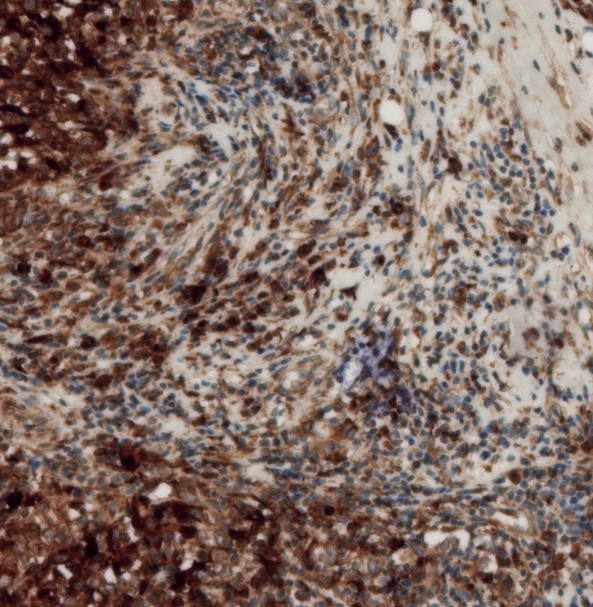

This year we had three students in the lab, and their job was to kick start our new project on LaNt in breast cancer. Over the course of their time in the lab, Eleanor, Marian and Louiza learned how to process tissue sections for immunohistochemistry and then how to image and analyse those sections. They also turned their hand to cell culture, growing breast cancer cell lines in a dish and then studying their invasive potential in a model of cancer metastasis.

Starting a new project and getting the first taste of real lab work is challenging but they all did amazingly well. The data they generated is really impressive in quality and exciting in their implications. They’ve kick started a new direction for the lab that we think could have real value in the diagnosis and treatment of breast cancer. More on this soon.